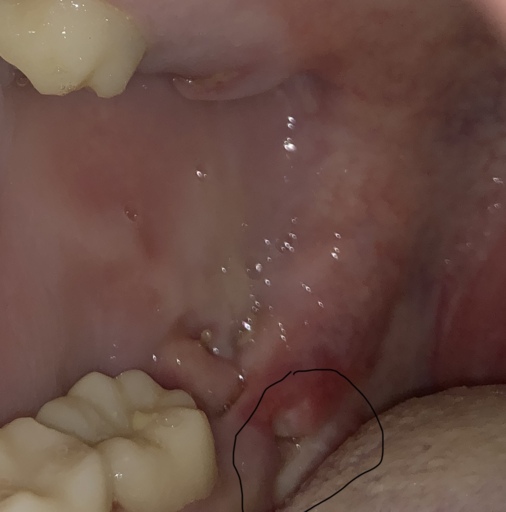

I had my back left wisdom tooth removed 72 hours ago and I can feel and see a large grey soft lump (size of a tooth). It's definitely very different to my first wisdom tooth removal which was plain sailing! I've followed all instructions with paracetomol and ibrorprofen and waited 24 hours until gentle salt water washes and gentle Cordosyl rinses. It extends whenever I do my rinses (feels like a lot of loose skin/tissue?!?). Any help would be greatly appreciated. I'm not in lots of pain but discomfort and the odour and taste in my mouth is deeply unpleasant.

Without a photo of the area it is hard to see exactly where the tissue is and to where it extends. Like any other area that bleeds on our skin, a scab is formed. The mouth is no different when new tissue is forming. It is best to check with the dentist or surgeon that performed the extraction to see if sutures were placed and if any collagen may have been added. This could be what is extending and not your tissue itself. The foul odor could be produced from decomposing food in the socket that is not being properly cleaned. Be sure you are rinsing with warm salt water several times a day to remove debris and taking prescriptions as written. Discomfort 72 hours after an extraction is normal, it should continue to get better everyday.